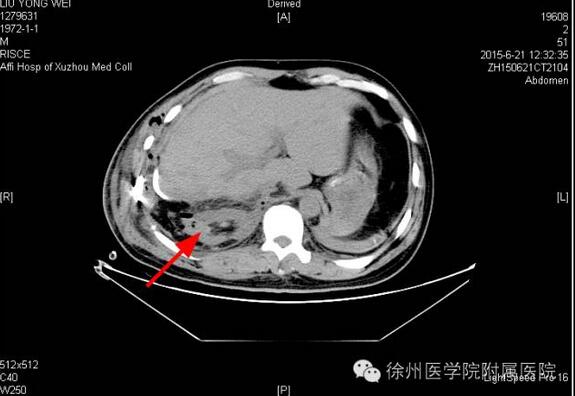

该声明称,患者手术时间是2015年6月20日,术后分别于2015年6月21日(术后第1天)和6月25日(术后第5天)的2次CT复查均显示该患者的右肾存在。

该声明还专门张贴了两张CT复查图。

图一2015年6月21日(术后第1天)CT,右肾如箭头所示。